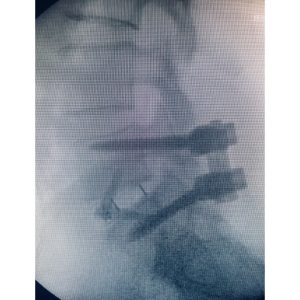

For this patient who had years of debilitating back pain, the solution was an ‘anterior-posterior’ or ‘front-back’ lumbar spine surgery (3rd photo). The surgery is also known as an ALIF (Anterior Lumbar Interbody Fusion) with posterior stabilization.